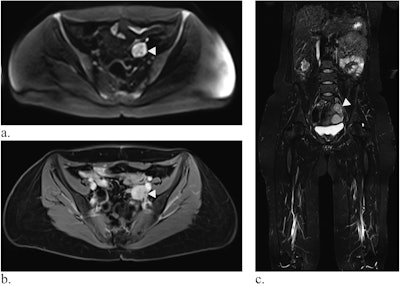

Whole-body MRI of a 39-year-old woman with LFS showing a mass in the small pelvis (white arrow) in diffusion-weighted imaging (a) and contrast-enhanced T1-weighted Dixon images (b, here: water-only image). In the coronal TIRM-sequence (c), the mass is visible, but difficult to differentiate from the intestine, emphasizing the value of diffusion-weighted imaging. Histology revealed a leiomyosarcoma.